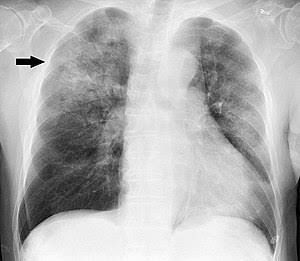

Pneumonia is an infection that inflames the air sacs in one or both lungs. The air sacs may fill with fluid or pus (purulent material), causing cough with phlegm or pus, fever, chills, and difficulty breathing. A variety of organisms, including bacteria, viruses and fungi, can cause pneumonia.